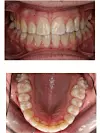

- Det er viktig å merke seg at vi ikke ønsker å skremme noen, men å opplyse, sa overtannlege ved tannklinikken, Hanne Komann, som la ut dette bilde av jentas munn, for å advare mot langvarig smokkbruk.

SE BILDER AV KRYSSBITT OG OVERBITT UNDER: